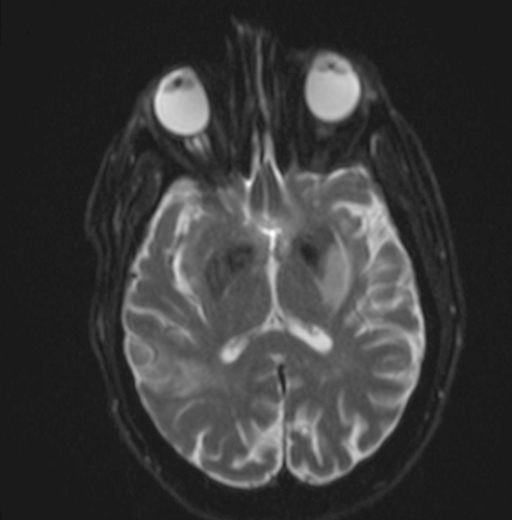

Radiology description

- CT unenhanced

- Early / acute signs: loss of definition between gray and white matter, cortical hypoattenuation and effacement of the sulci (Radiology 2005;235:444)

- Loss of the insular cortex in acute middle cerebral artery (MCA) infarcts (Radiology 1990;176:801)

- Hyperdensity of the MCA (i.e., hyperdense artery sign) is observed in 30 - 40% of patients with acute MCA infarcts (Stroke 1992;23:317)

- Chronic infarcts show cavitation sometimes with mineralization

- MRI

- Diffusion weighted imaging (DWI): hyperintense signal in the acutely infarcted tissue; low signal on apparent diffusion coefficient (ADC) map

- Infarcts are often T2 hyperintense

- Collateral flow on FLAIR: linear or serpentine hyperintensities distal to the site of obstruction (Neurology 2009;72:1134)

- Perfusion weighted imaging (PWI) - DWI mismatch: used to estimate the salvageable tissue (i.e., penumbra) in acute infarct (Neuroimaging Clin N Am 2021;31:177, AJNR Am J Neuroradiol 2015;36:32)

- Ischemic areas on PWI are compared with areas shown by DWI (i.e., the infarct core or nonsalvageable tissue); the mismatch represents the volume of salvageable tissue with reperfusion therapy

- Chronic infarcts show absence of contrast enhancement in strokes older than 4 months (Radiographics 2012;32:1285)

Radiology images